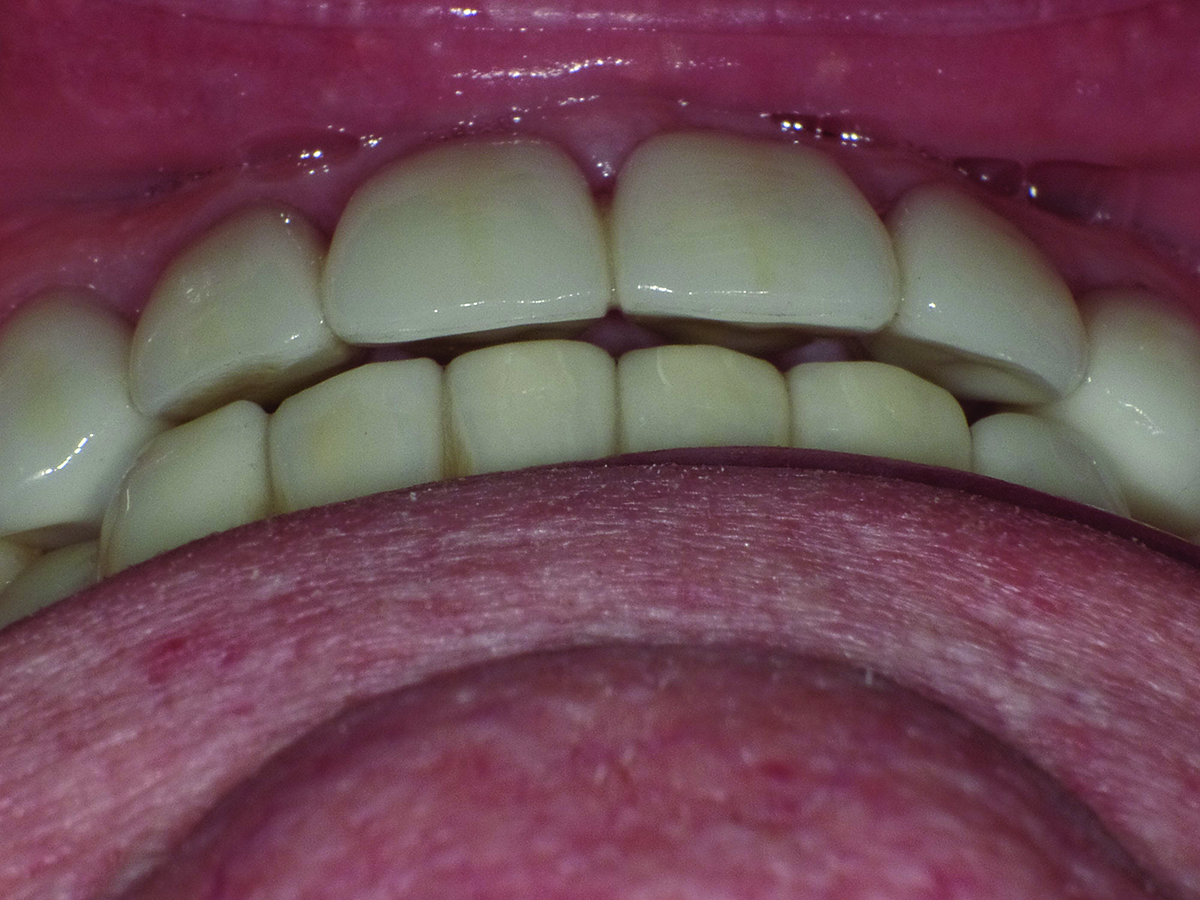

Patient in repose, post-treatment.

Figure 13

When the patient returned 7 months later, the anterior teeth were better aligned, an overjet was created, and the midline was centered (Figure 12). The preparations on teeth Nos. 6 through 13 and 22 through 27 for lithium-

disilicate crowns were completed, scanned, and temporized. The temporaries were used to verify that the desired esthetic changes were accomplished. The same chairside procedure was used for temporization as with the posterior molars. The amount of display of the anterior teeth was increased 1 mm to be visible in repose. A stump photograph was taken with the shade guide for the laboratory. Photographs were taken for lab communication, and the patient went to the lab for custom shading.

Three weeks later, the patient returned to the office for the cementation procedures. After clinical assessment of proximal contacts, marginal integrity, and patient approval of the esthetics and speech patterns, the crowns were cemented. The maxillary incisors had a pleasing display in repose (Figure 13). The same cementation protocols were used as in the initial restorative phase, except silane was applied to the internal surfaces of the crowns. Occlusion was verified, ensuring no functional inter-

ferences on the anterior teeth (Figure 14). Shimstock was used to verify stable centric occlusal MIP contacts on the posterior teeth. Articulating film verified positioning of the cusp-to-fossa relationships with a minimum of one stable contact for each tooth, and 200-µm blue paper was used to verify that there were no lateral streaks when the patient was sitting up at a 45-degree incline while chewing on the paper. A post-treatment full-face photograph is shown in Figure 15.